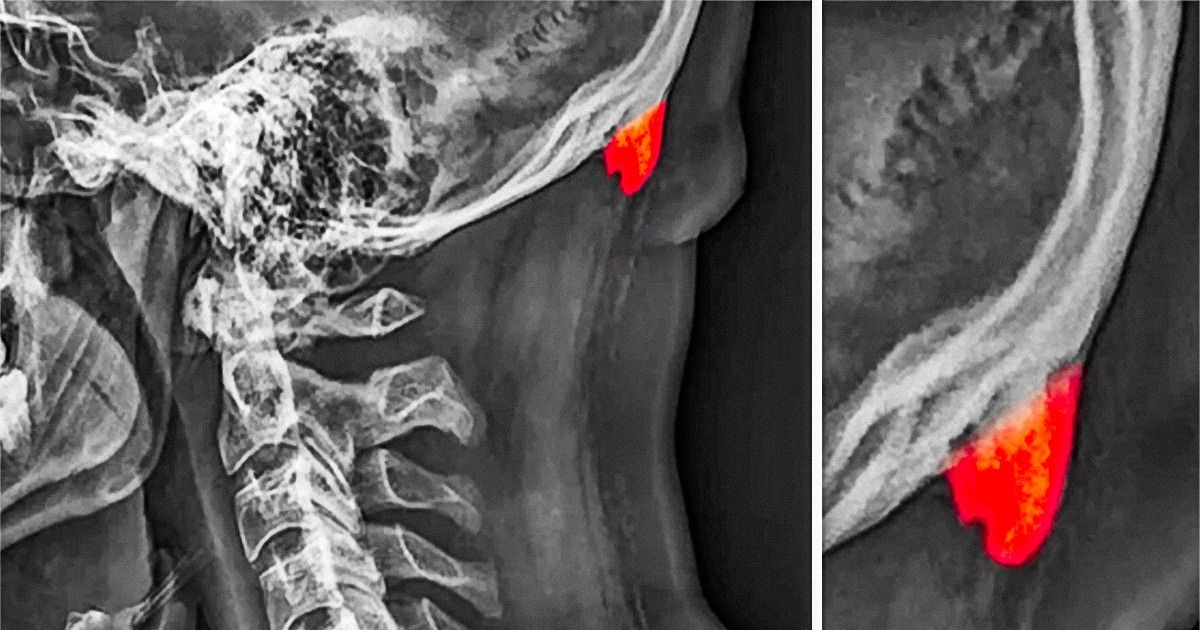

Sabe-se que crescimentos ósseos incomuns, ou esporões ósseos, ocorrem em pessoas idosas, mas o estudo, realizado por David Shahar e Mark G. L. Sayers, apresentou detalhes novos e chocantes. Depois de coletar e analisar dados de 1.200 pessoas de ambos os sexos, entre 18 e 86 anos, os pesquisadores verificaram que, por alguma razão, a exostose — conhecida justamente como esporão ósseo — está aparecendo em adolescentes e adultos jovens e o número de pessoas com esse problema está aumentando.

Curiosamente, esses esporões ósseos estão crescendo na parte de trás dos crânios e têm a aparência de chifres. Por isso, alguns meios de comunicação têm publicado a notícia de que os jovens estão produzindo “chifres” na parte de trás do crânio. E o motivo seria o uso de telefones celulares e de outras tecnologias por longas horas. Mas essa é uma informação falsa. Evidentemente essas protuberâncias não são chifres. E não são os celulares que devem ser diretamente responsabilizados por isso.

O esporão ósseo semelhante a um chifre foi encontrado em mais de 40% das pessoas entre 18 e 29 anos avaliadas e esse fato é muito chocante. Outra causa possível para o mesmo problema pode ser a má postura. Já se sabe que ela afeta o formato da nossa estrutura esquelética. Uma hipótese é a de que em alguns jovens adultos o pescoço e a coluna tenham ficado tão inflamados que o corpo esteja produzindo novos ossos para sustentá-los.